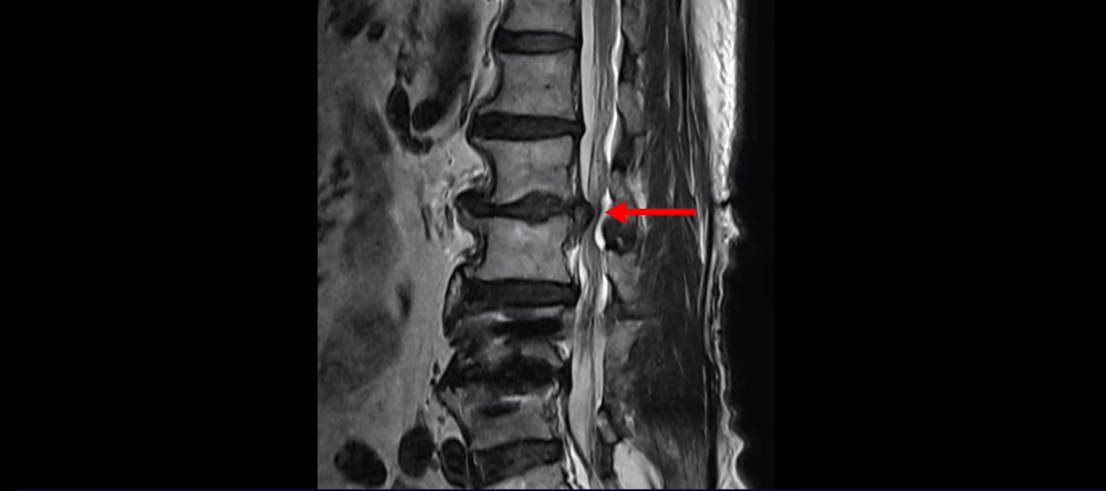

이분 허리 MRI를 보면서 간단히 설명드린 후 유합술 이후 인접마디에 문제가 생긴 환자분들이 왜 추가적인 수술을 서두르기보다는 허리기능을 살려주는 근육신경재활치료를 받는 게 좋은지, 또 치료는 어떻게 하는 게 좋은지 자세히 설명드리겠습니다. 이분 MRI를 보면 4번 5번에 나사가 박혀있습니다.

이렇게 나사가 박혀있으면 그 위나 아래에 문제가 많이 생기고 그걸 인접분절질환이라고 부릅니다. 이분도 유합술을 받은 그 윗마디인 2번 3번에서 디스크가 터져 밀려나와서 수술을 받았는데

이게 수술 후 사진인데도 여전히 척추관은 좁습니다.

나사 박은 마디 위쪽에 수술을 받았지만 수술 후에도 전혀 통증이 좋아지지 않고 다리에 힘도 빠져서 워커를 잡고 겨우 걷는 상태였습니다. 이렇게 유합술 이후 그 위나 아래에 문제가 생기는 인접분절질환은 모든 척추질환 중 가장 치료가 어려운 질환 중 하나로 꼽힙니다.